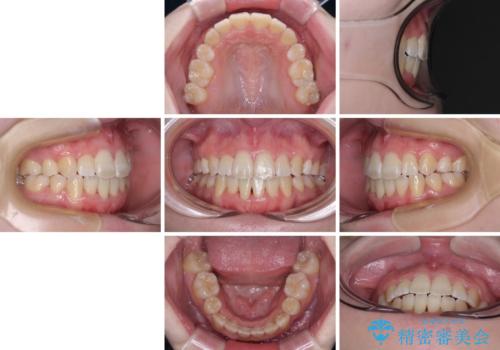

上下非接触で突出した前歯 ワイヤー装置による抜歯矯正

- 上下前歯の隙間と口元の出っ張った感じを気にして来院された患者様です。

上下の隙間は舌突出癖によるもので、またその癖により前歯が前方に出ている状態でした。

口元の出っ張りを改善するため、上下左右第一小臼歯4本を抜去し、ワイヤー装置にて矯正治療を行うこととしました。

舌の突出癖を改善するためのトレーニングをしっかりと行っていただいたことで、比較的スムーズに治療を進めることができました。

口元の突出感もしっかりと改善することができました。